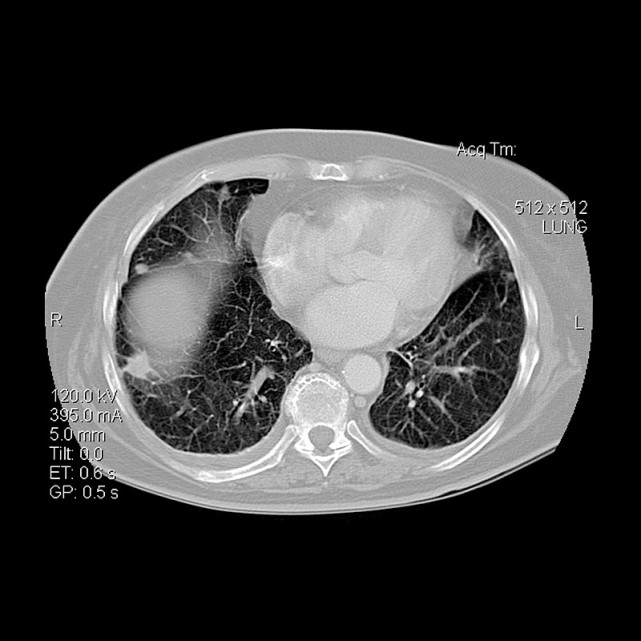

1. 对于肺癌高危人群,建议行低剂量螺旋 CT筛查。建议尽可能使用 64 排或以上多排螺旋CT进行肺癌筛查,扫描范围为肺尖至肋膈角尖端水平。基线 CT 扫描以后,根据病灶具体情况(形态、大小、边界等特征),建议至专科医院咨询具体下一步诊疗计划;

2. 若检出肺内结节,根据结节不同特征,磨玻璃、亚实性、实性结节及多发结节的具体情况进行低剂量CT复查;